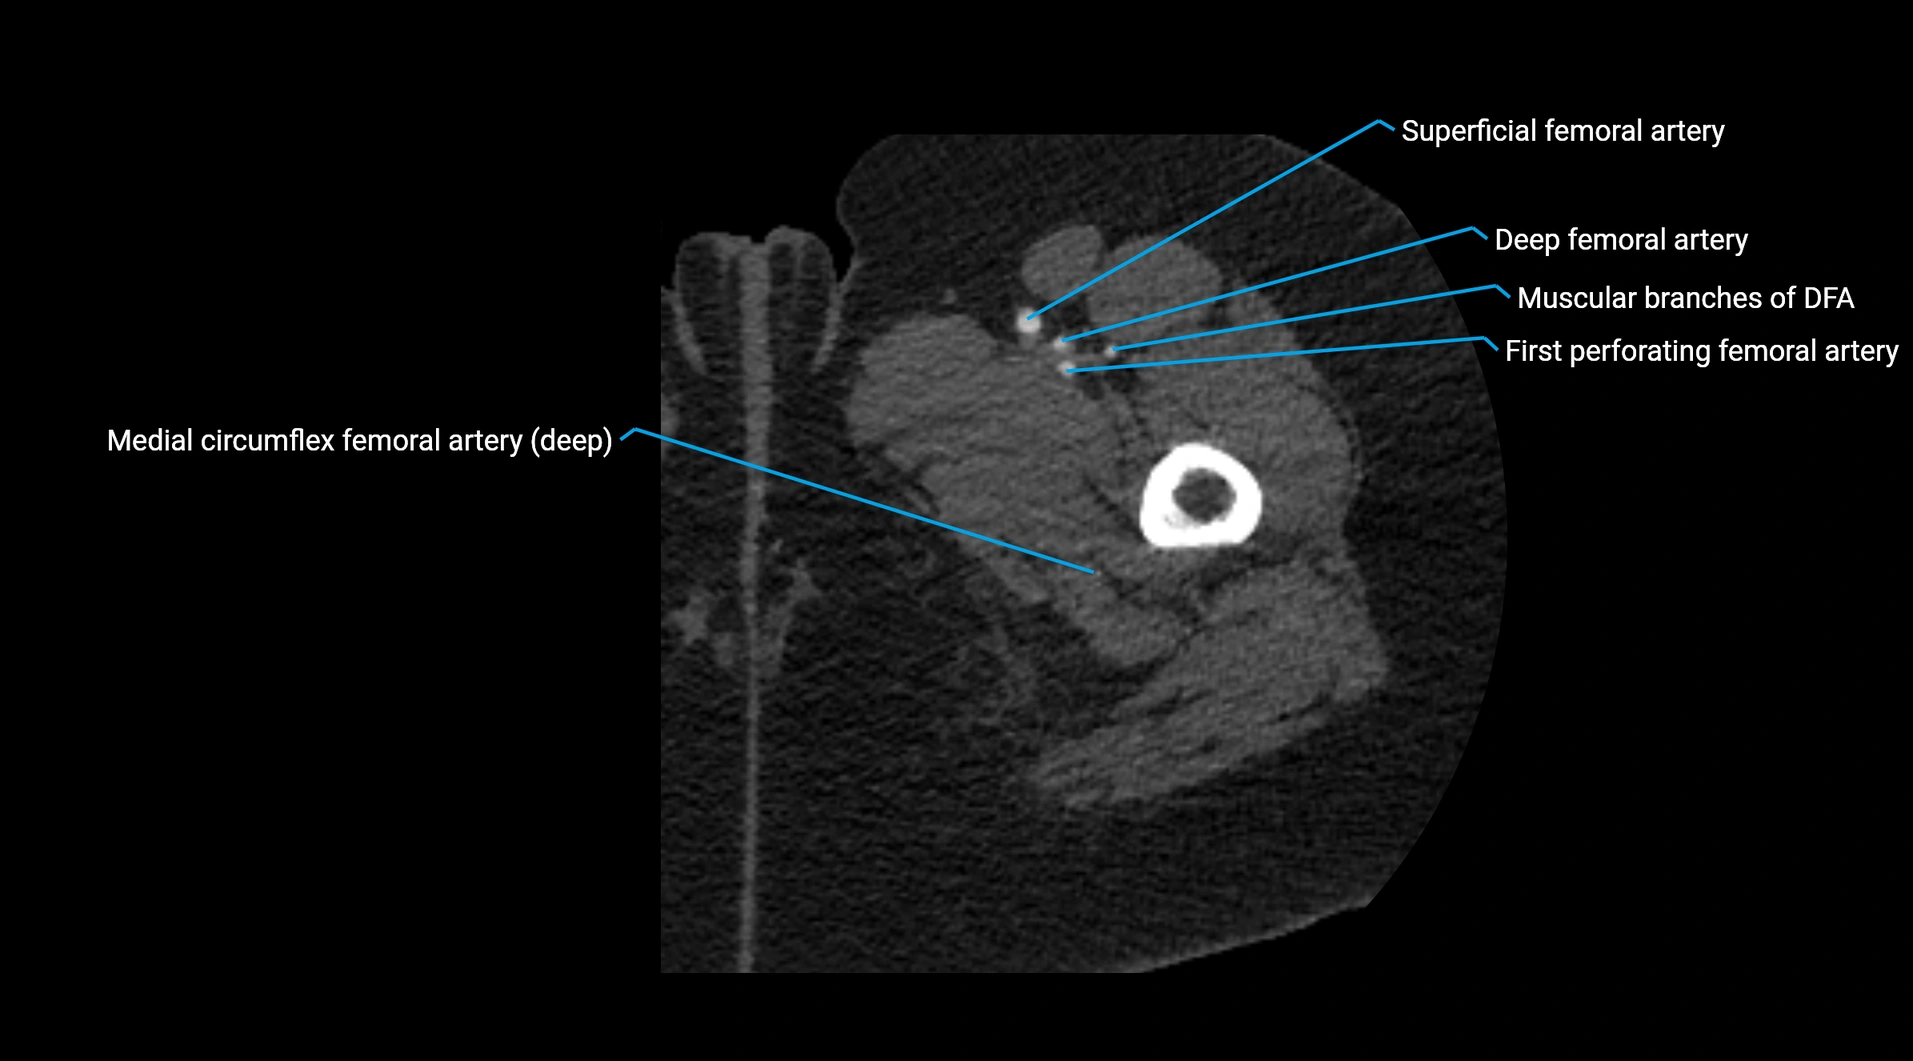

Contrast-enhanced CT (CTA):

• Gold standard for abdominal aortic imaging

• Provides excellent detail of lumen, wall, aneurysm, thrombus, and branch vessels

• Multiplanar and 3D reconstructions help in aneurysm measurement, stent graft planning, and dissection evaluation

• Detects acute rupture, traumatic injury, or occlusion with high sensitivity